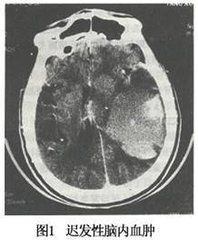

腦CT特點是血腫呈混雜密度,血腫內有陳舊出血和新舊不同時間的出血,並呈擴張性占位性病變表現。MRI也有助於診斷。

遲發性腦內血腫的診斷主要依靠反覆的CT掃描。其病史診斷要滿足以下4點:1.無腦血管病。2.有明確頭外傷史。3.傷後第1次CT掃描無腦內血腫。4.經過一個好轉期或穩定期後出現卒中發作。